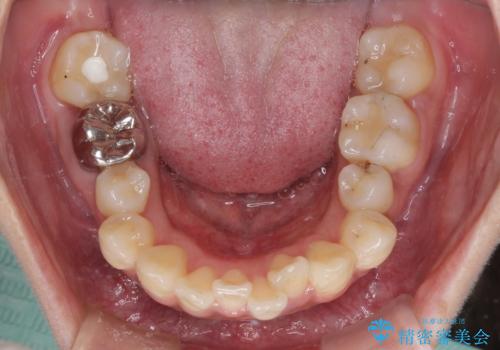

左下奥歯にむし歯が認められるため、矯正治療後にセラミックインレーにて修復治療を行うこととしました。

4本の歯を抜歯したことで、飛び出していた口元が引っ込み、横顔が大きく改善されました。